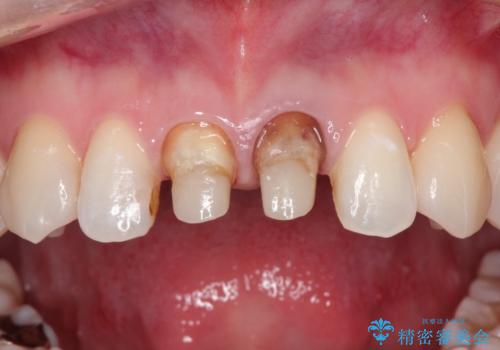

前歯の根元が黒い オールセラミッククラウンの装着による改善

- 10年前ほどに前歯に装着されたセラミックの根元の方が黒くなってきたのが気になるとのことで来院されました。

上顎の前歯の歯茎が下がり、ご自身の歯が露出している状態でした。

金属の土台をファイバーコアに交換後、オールセラミッククラウンを装着する計画としました。